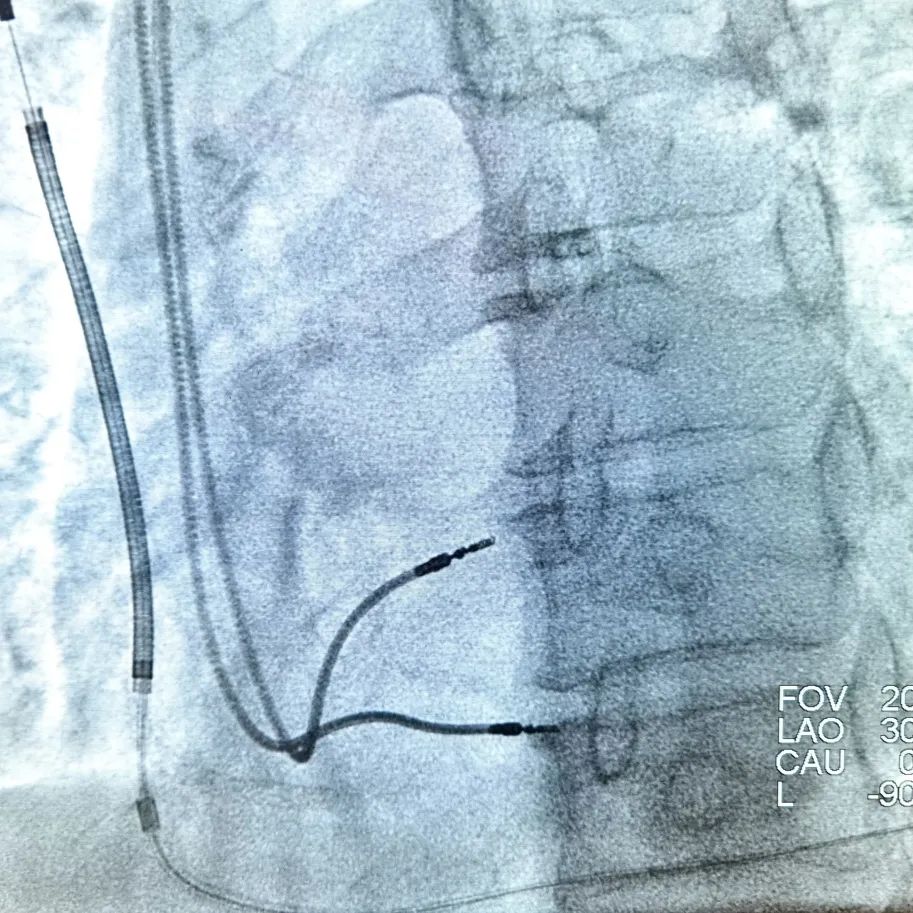

该手术需要注意S-ICD的“全皮下”特性和CCM的两根导线摆放位置,传统ICD感知的是腔内局部的电活动,而S-ICD所感知的是类似于体表心电图。而CCM是在感知到QRS波的绝对不应期发挥作用,二者工作模式有交互,尤其是S-ICD会感知CCM工作状态下对QRS波的改变,而增加“噪音N”的比例记录。姚娟教授凭借丰富的植入经验,术中首先植入S-ICD,植入后抓取模板,优化向量,随后暂时关闭S-ICD抗心动过速功能。再植入CCM,两根心室导线于右室间隔中低位,两根导线间距大于2cm,两根导线感知阈值均大于10mv,起搏阈值均为0.6v,阻抗分别为560Ω和700Ω,表明导线植入在健康的心肌上。测试完连接CCM植入,调整参数在保证正常发送比率的同时减轻对S-ICD的干扰识别,开启S-ICD功能,经过双机器同步程控测试,消除了S-ICD对CCM的工作状态识别为“噪音N”的干扰,二者均正常发挥功能。CCM联合S-ICD一站式植入顺利完成,手术全程用时2小时。